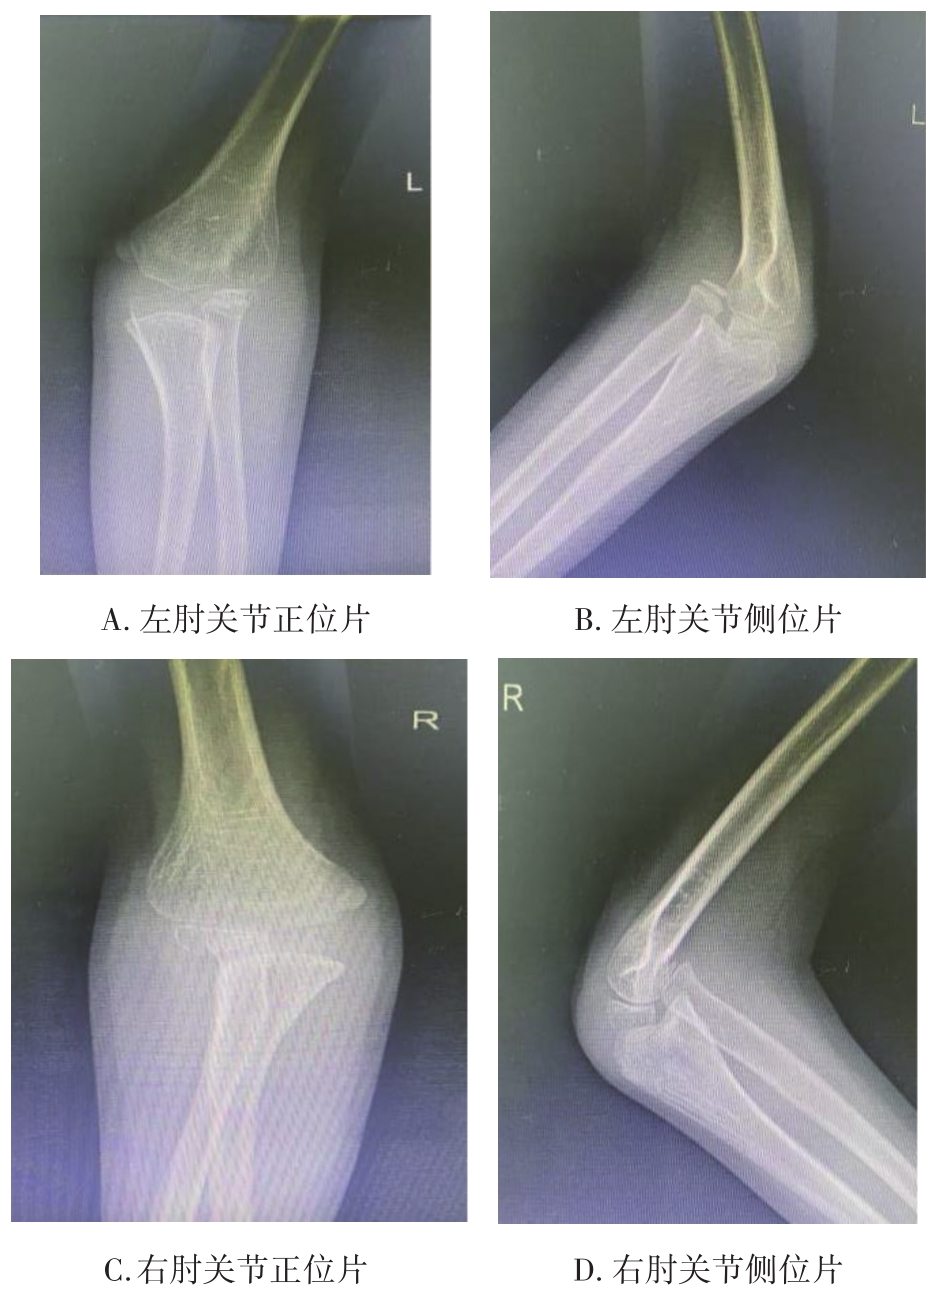

• 3D打印下精准截骨术治疗先天性尺桡关节脱位1例报道

2023, 48(5):618-620. DOI: 10.13406/j.cnki.cyxb.003218

摘要 (98) HTML (49) PDF 4.15 M (219) 评论 (0) 收藏

摘要: